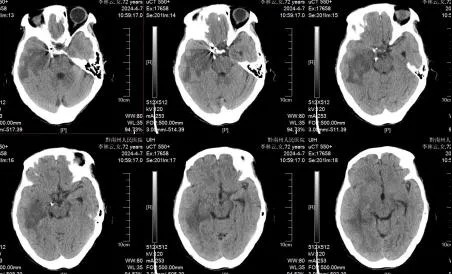

针对李姥姥术后恢复情况,神经外科团队联合临床营养科制定了快速康复的诊疗方案。因患者颅内动脉瘤破裂伴蛛网膜下腔出血且高龄、意识不清、长期卧床有肺部感染、消瘦、贫血等多个问题,医务人员给予纠正贫血、抗生素保护下进行俯卧位通气、量身定制营养餐、血性脑脊液置换避免发生脑积水、早期下床康复活动等快速康复治疗。李姥姥顺利度过危险期,无继发脑积水,术后7天拔除脑室引流管,术后13天复查头颅CT平扫提示蛛网膜下腔出血已吸收,意识完全清醒,无神经外科功能损害表现,16天就达到治愈出院标准。

术后13天复查头颅CT平扫提示蛛网膜下腔出血已吸收